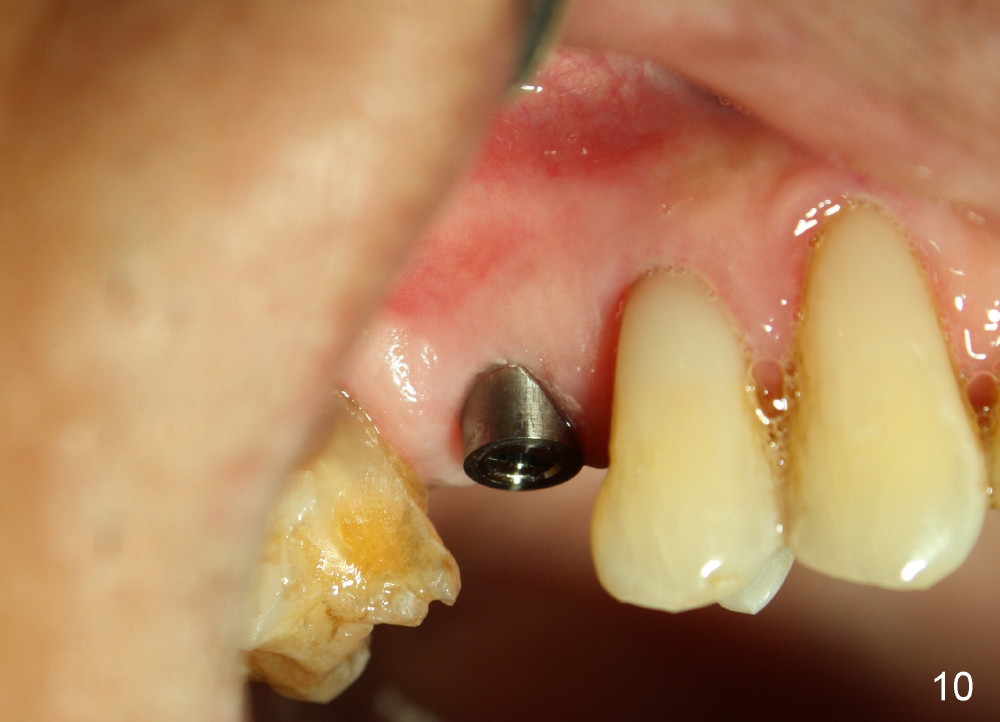

A 72-year-old man is a bruxer with #3 cusp fracture with chronic periapical radiolucency (Fig.1 *) and #4 acute crack. It appears reasonable to take care of emergency (#4 extraction and immediate implant (Fig.3-7: 4.5x20 mm, 45 Ncm)) followed by root canal therapy or extraction for #3. Eight (Fig.8) and 14 (Fig.9-11) days postop, the patient is doing fine and the wound heals normally. But he does not agree any treatment for #3, since it is asymptomatic in spite of a fistula associated with the tooth (Fig.8,9 >). Three months postop, the patient is still asymptomatic and is ready for #4 restoration since the tooth #28 cracks. Follow-up PA shows the persistent distal gap (Fig.12 >, as compared to Fig.4), accompanied with crestal bone resorption (*). Clinically the implant has mild mobility and light tenderness. The patient still refuses #3 treatment. It appears that the implant has failed to osteointegrate. In brief, do not place an immediate implant next to active infection.